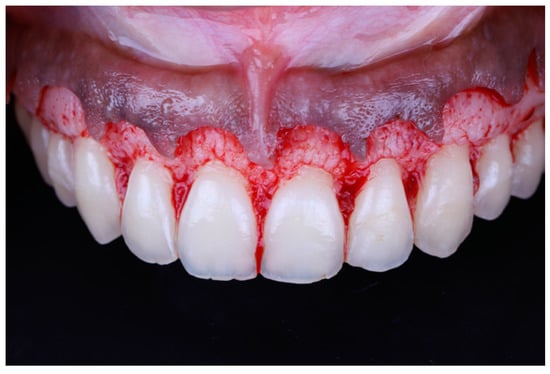

Local anesthesia (xylocaine with epinephrine 1:100.000) was administered via buccal infiltration. The guide was then placed. Using a 15c blade and following the upper border of the window of the guide, an internal bevel incision was made from right to left first molar teeth (Figure 5). The guide was then removed and a second incision was made in a sulcular fashion. The secondary flap was removed using a Youger-Good curette while visualizing the new crown lengths (Figure 6).

Figure 5.

Surgical incision based on the guide.

Figure 6.

Tooth length after gingival excision.